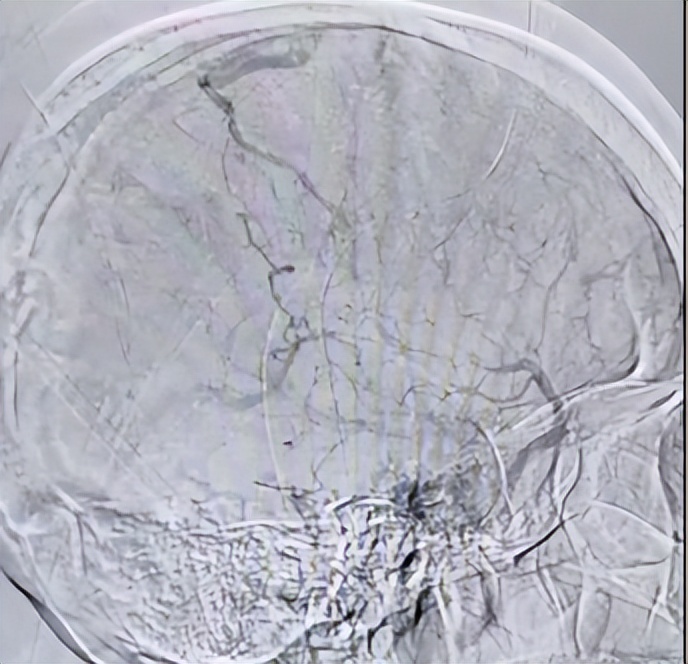

术中见“脑动静脉回流时间明显延长,上矢状窦几乎全程血栓,右侧横窦中远段及窦汇血栓,左侧横窦发育不全”,介入团队一次抽吸快速清除出颈静脉和右侧横窦的大量血栓,再通过抽吸和支架取栓技术取出了上矢状窦内的大量血栓。造影复查见“脑动静脉回流明显好转,上矢状窦、窦汇及右侧横窦、乙状窦血流通畅”。

▲脑内静脉窦恢复正常回流

▲颅内静脉窦通畅 未见血栓